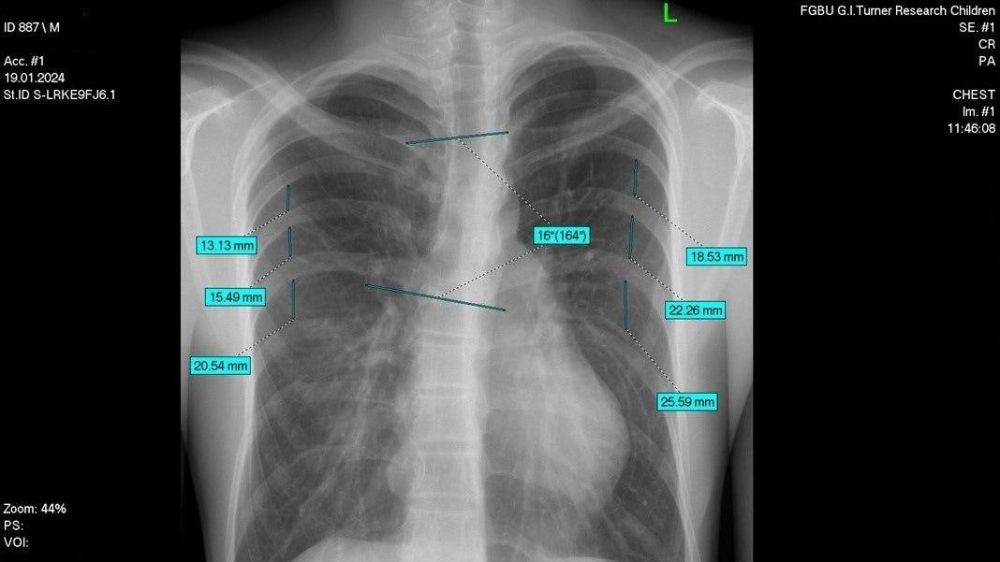

Специалисты Национального медицинского исследовательского центра (НМИЦ) детской травматологии и ортопедии имени Г.И. Турнера Минздрава России провели высокотехнологичную операцию 17-летнему пациенту из Луганской Народной Республики, сообщили в...